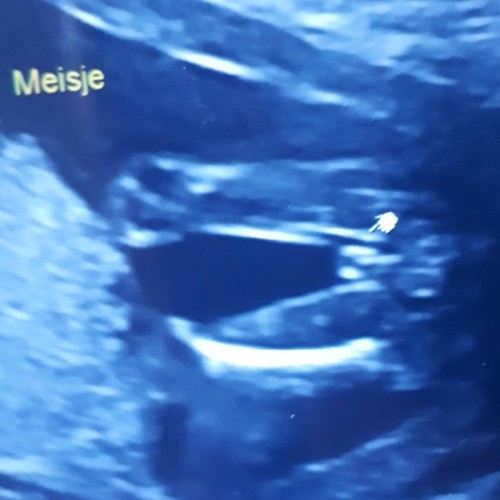

Ik heb nog even contact met haar gehad en ze stuurde me ook de nub nog toe en het beeld in 3d wel mogen we de 12e nog eens terug omdat ze toe gaf zelf ook te hebben getwijfeld en bang is dat onze twijfels daar door komen.. al ben ik aan de hand van de nub en het 3d beeld echt zeker dat het een meisje is toch fijn dat we even extra mogen kijken